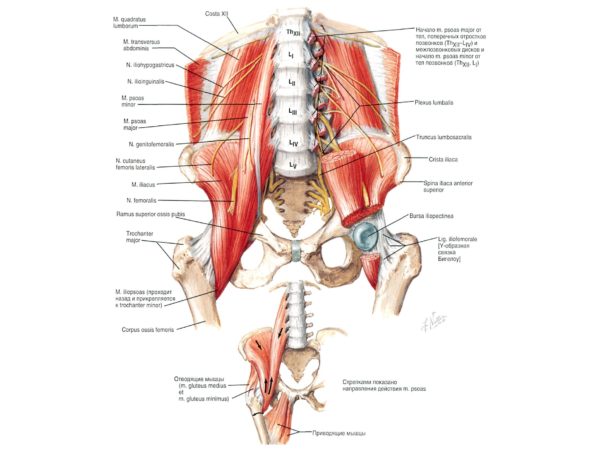

- Цельный позвоночный столб окружает со всех сторон мышечная ткань. Благодаря мышцам удается избежать большинства механических повреждений, которые непременно возникли бы, не будь у позвоночника мышечной защиты. Также ткань уменьшает нагрузку, выпрямляя спину и моделируя работу органов, расположенных внутри тела.

Анатомия поясничного отдела

Мышцы спины

Поясничные позвонки наиболее массивные и крупные во всём позвоночнике, с увеличением от первого поясничного к пятому, что объясняется максимальной нагрузкой на нижний отдел позвоночника. Позвонки грудного отдела и крестец малоподвижны, что требует от позвонков поясничного отдела повышенной подвижности. Пять поясничных позвонков человека и крестец образуют пять позвоночно-двигательных сегментов, что обеспечивает принципиальную возможность поворотов корпуса в стороны, движений корпуса в сагиттальной и фронтальной плоскости, а также комбинированные повороты и наклоны. Наличие сильных мышц поясницы помогает осуществлять движения даже с дополнительной нагрузкой.

Воздействия мышц живота служат либо для того, чтобы зафиксировать позвоночник, либо заставить его двигаться. Они осуществляются на поясничном отделе позвоночника или на его нижнем спинном отделе.

Это воздействие никогда не является прямым, поскольку мышцы живота не крепятся на позвоночнике. Поэтому они увлекают его в результате воздействия на таз или грудную клетку.

Воздействие мышц живота на поясничный отдел позвоночника происходит до нижних спинных позвонков. При сгибании амплитуда максимальна на грудо-поясничном уровне (D10-L2), в очень подвижной в этом направлении области. При боковом наклоне движение распространяется еще ниже.